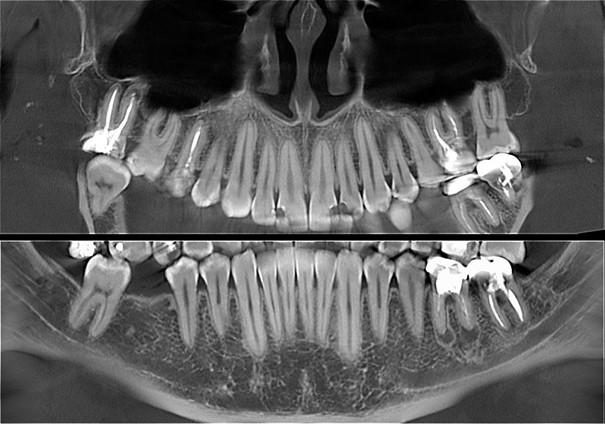

Компьютерная томография челюсти (КТ) представляет собой современный метод рентгеновской диагностики, который позволяет получить трехмерное изображение всей зубочелюстной системы или ее отдельных участков. Серия полученных снимков предоставляет стоматологу возможность детально изучить ткани с разных ракурсов. Эта методика отличается высокой степенью информативности.

Уникальное программное обеспечение объединяет отдельные изображения в трехмерный снимок. Диагност имеет возможность настраивать оборудование, изменяя интенсивность излучения и разрешение для достижения наилучших результатов.

Процедура ортопантомографии обеспечивает меньшую лучевую нагрузку на организм, составляющую 15 микрозиверт в час, в отличие от компьютерной томографии, где этот показатель варьируется от 70 до 90 мкЗв. Однако при проведении ОПТГ специалист получает лишь один двухмерный снимок, тогда как при компьютерной томографии зубов формируется трехмерное изображение, состоящее из множества послойных «срезов», что позволяет избежать искажений. В процессе одной съемки на дентальном томографе можно получить до 300 различных изображений.